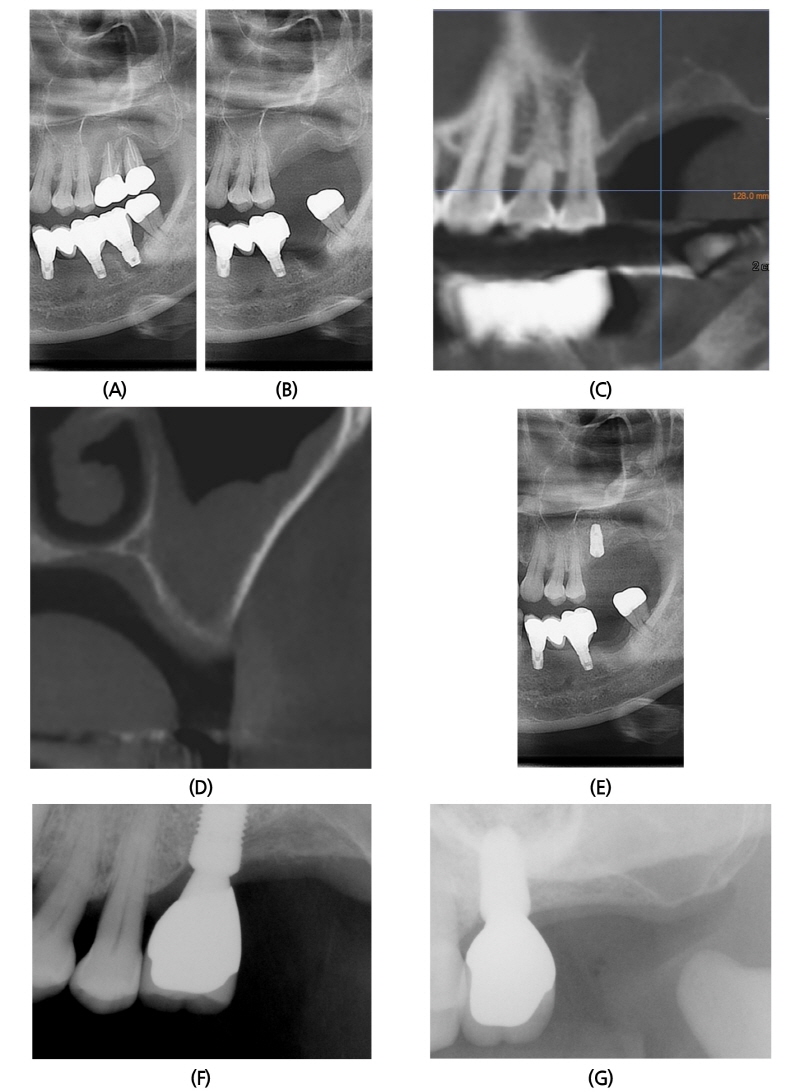

2015년 3월 9일 56세 남성이 좌측 위 어금니 부위가 불편하여 발치하고 임플란트가 가능한지 상담을 위해 본과로 내원하였다. 환자는 특기할 전신질환 및 수술 병력이 없었으며, 임상 검사 및 방사선학적 검사상 #26, 27, 37i 부위에 중증의 치조골 흡수를 보이고 있었다(Fig. 1A). #26, 27 치아는 각각 2급, 3급의 치아 동요도를 보이고 있었으며, #37i는 implant 주위로 pus discharge 되고 있었다. 2015년 4월 6일, 국소마취하 #26, 27 단순 발치 시행하였다(Fig. 1B). 수술 전 촬영한 CBCT (Cone Beam Computed Tomography) 소견상, #26 부위는 치조정에서부터 상악동 하연까지 2 mm정도 두께만 남았으며 치조골은 buccal에서 palatal 방향으로 경사져 있었다(Fig. 1C, 1D). 2015년 9월 15일 좌측 상악동 골이식술 및 #26 부위 임플란트 1차 수술을 동시에 진행하였다. Lateral approach 시행하였으며, bone window는 carbide round bur를 사용하여 cortical bone window를 채득하였다. 상악동 거상시 membrane의 전방부가 sharp한 모양이었으나, tearing되지 않도록 조심하여 lifting하였다. 골이식재는 ICB® (Irradiated Allogenic Cancellous bone & Marrow, (주)푸르고 바이오로직스)1.0 g과 MBCP® (Micro-Macro Biphasic Calcium Phosphate, (주)푸르고 바이오로직스) 0.5 g을 혼합하여 사용하였으며, opening하면서 채취한 cortical bone으로 bone window를 다시 덮어주었다. Bone window 의 경계 부위는 동종골과 합성골로 gap 없이 채워넣었다. 차단막은 사용하지 않았다. 임플란트는 #26 부위에 Implantium® (Ø4.8 × 10 mm, drilling Ø3.8 mm)을 식립하였으며, #27 후방 부위에 alveoloplasty 시행하면서 채취한 자가골을 #26i fixture뒤에 anterior-posterior방향으로 groove처럼 존재하던 defect부위에 이식하였다(Fig. 1E). 4달 후 #26i에 대한 임플란트 2차 수술 시행하였으며, 골조직은 양호한 치유양상을 나타내었다. 수술 후 6개월, 18개월 후에도 임상적, 방사선학적으로 양호한 상태를 보이고 있다(Fig. 1F, 1G).